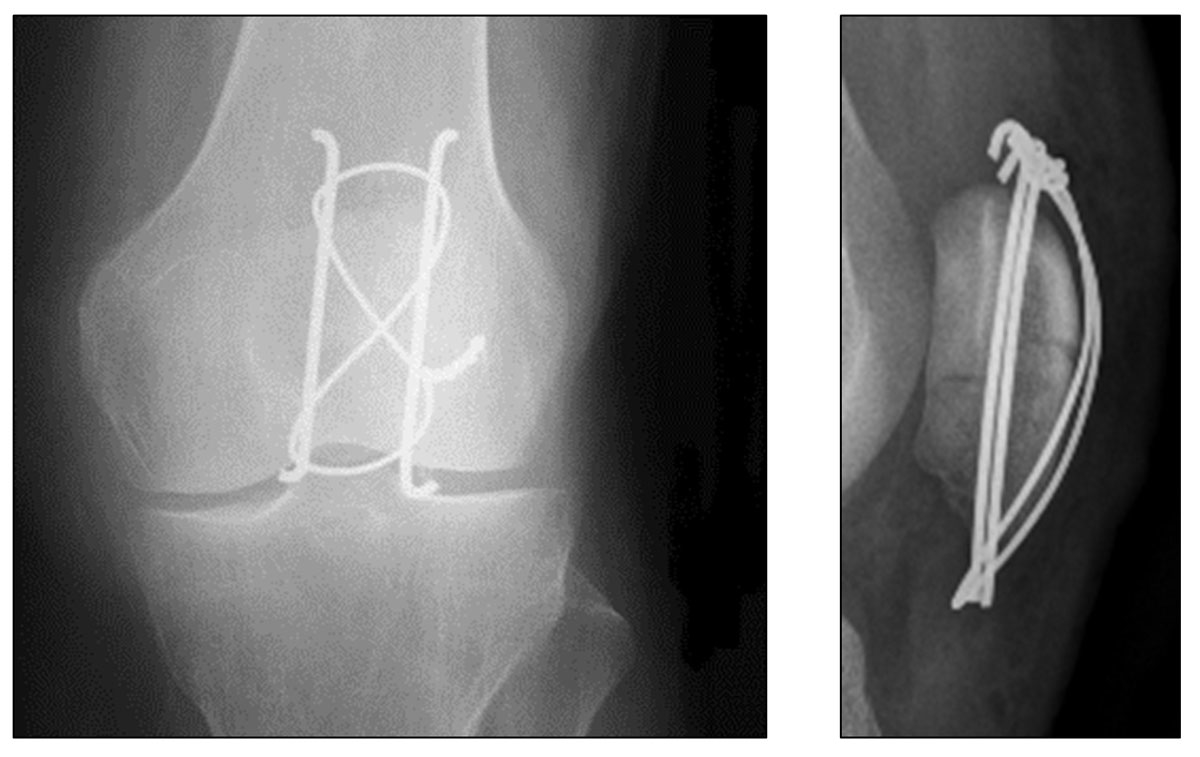

From www.researchgate.net

Preoperative Xrays of a comminuted patella fracture (above). 3 months Return To Sports After Patellar Fracture For athletes, the journey back to the field, court, or track is fraught with hurdles, requiring more than just physical healing. After patella fracture most common complication is the knee stiffness. It was attempted to answer the following two questions: Patella fracture can be treated without surgery (if fracture is undisplaced) or with surgery (for displaced fracture fragments). (1) how. Return To Sports After Patellar Fracture.